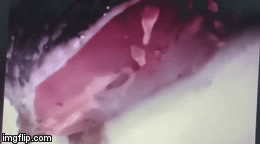

Tại đây, bệnh nhi được các bác sĩ Khoa Liên Chuyên khoa chẩn đoán trẻ bị viêm tai phải do dị vật sống. 20 con giòi (ấu trùng ruồi) được lấy ra khỏi tai phải của bệnh nhi. Rất may là thính lực của trẻ không bị ảnh hưởng.

Thông tin trên Sức khỏe & Đời sống, bác sĩ Trần Minh Tấn - người trực tiếp điều trị cho cháu L. cho biết, khi tiếp nhận bệnh nhi, các bác sĩ đã nội soi kiểm tra tai thì thấy trong tai phải của cháu có rất nhiều ấu trùng ruồi (con giòi).

Bệnh nhi sau đó được các bác sĩ thực hiện thủ thuật lấy khoảng 20 con giòi, xác ruồi trong tai và vệ sinh tai sạch sẽ.

Tuy nhiên, do màng nhĩ phù nề, xung huyết và tiết dịch nên trẻ được chỉ định nhập viện để tiếp tục theo dõi.